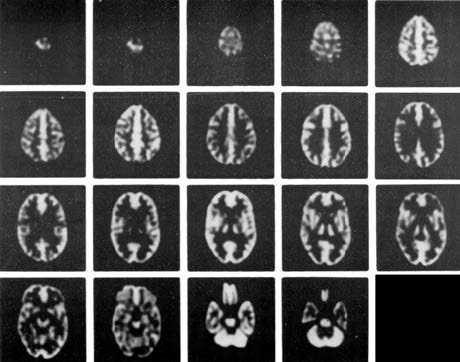

Hoffman 3-D腦模體,霍夫曼腦模體主要特點:

-在腦部SPECT及腦部PET的研究中,從解刨學角度精確的模擬放射性分布;在MRI研究中,精確模擬質子密度及馳豫參數打的分布

Anatomically accurate simulation of radioactivity distribution for brain SPECT and brain PET studies* and distribution of proton density and relaxation parameters for brain MRI studies

-在血流和代謝研究中模擬正常灰質和白質的4:1攝取率(按部分體積效應模擬)

Simulates 4:1 uptake ratio (by partial volume effect) seen for normal gray and white matter in flow and metabolic studies